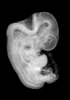

Human Embryo Logo

Carnegie Stage 18 (44 post-ovulatory days)

MRI Slice Selector